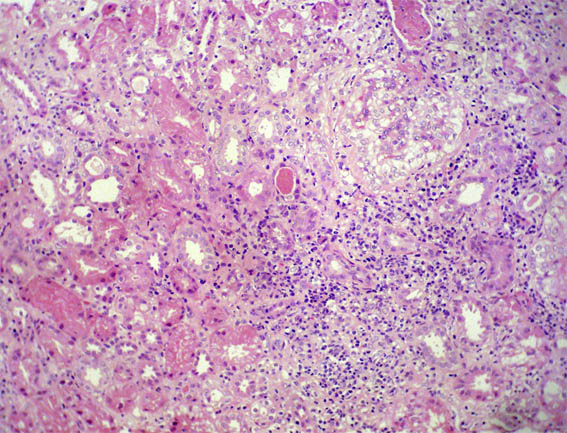

A renal biopsy was carried out. See the images:

Figure 1. H&E, X100.